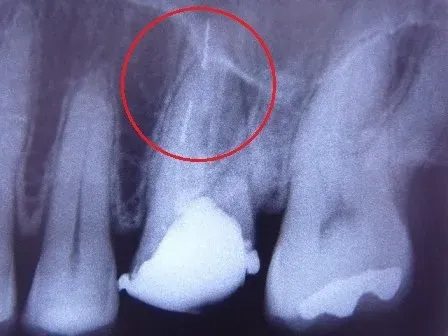

▶︎治療で使われる細い金属の破片が歯の中に取り残されている

▶︎歯の根管の壁に穴があき骨の方まで貫通してしまう(パーフォレーション・穿孔といいます)

など、手を加えるほど感染やトラブルの可能性が高まり、成功率はどんどん下がっていくこととなります。

パーフォレーションを起こした場合、顎の骨への細菌感染といったリスクも高まるため、多くの場合抜歯が必要になります。

複雑に入り組む歯の根の内部

歯の内部で取り残された器具